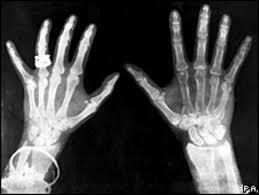

En este año nacieron los denominados rayos x, el alemán Conrad Rontgen, un físico que de forma accidental estaba haciendo experimentos usando tubos de Crookes y se dio cuenta que unos raros rayos estaban atravesando el papel y también el metal. Esto provocó en él una profunda investigación durante muchas semanas.

Lo que observó entonces fue que tras cubrir el tubo de Crookes con un cartón negro con la finalidad de eliminar la luz visible, se dio cuenta que un aparente resplandor amarillo-verdoso -

En 1895, Wilhelm Róntgen, al hacer pasar una corriente

eléctrica de alto voltaje a través de un tubo vacío, observó fortuitamente, en unos cristales de sal de bario próximos, que éstos

resplandecían con brillo fluorescente. Colocó su mano entre el

tubo y las sales y vio que aquélla, con la silueta de los huesos de

sus dedos, proyectaba su sombra sobre las sales. -